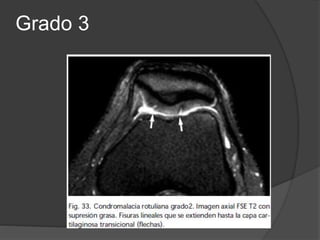

Condromalacia

 El grado se determina por artroscopía.

 Grado 0: Normal.

 Grado 1: Reblandecimiento del cartílago.

 Grado 2: Ulceración poco profunda, menor del 50% del espesor.

 Grado 3: Ulcera profunda, mayor del 50% del espesor, pero que

no se extiende al hueso.

 Grado 4: Ulcera con exposición del hueso subcondral.

Grado 3